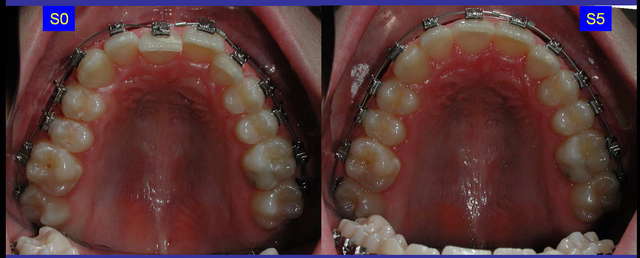

vue occlusale

Capturer 2 2 ftamlv - Eugenol

18/03/2006 à 12h41

superbe;

val il me semble que sur "capturer 3", la 25 soit absente. Est ce le meme cas?

carie bout

18/03/2006 à 12h48

autant pour moi, le samedi....

c'est la 23 qui est absente.

agenesie, extraction, ankylose

val

18/03/2006 à 14h38

23 a été extraite par le précédent praticien car elle était ectopique et que 24 allait prendre la place.

Le problème est que cette extraction, discutable pour le moins, n'a pas été suivie par l'extraction symetrique d'une PM <.

on se retrouve avec une asymétrie des milieux, une supra, de la CL II....avec 5 semestres déjà effectués !!!

Une reprise de TT s'impose, avec avulsion compensatoire de 45.

Se souvenir qu'une avulsion de canine non compensée est le début des emmerdes.